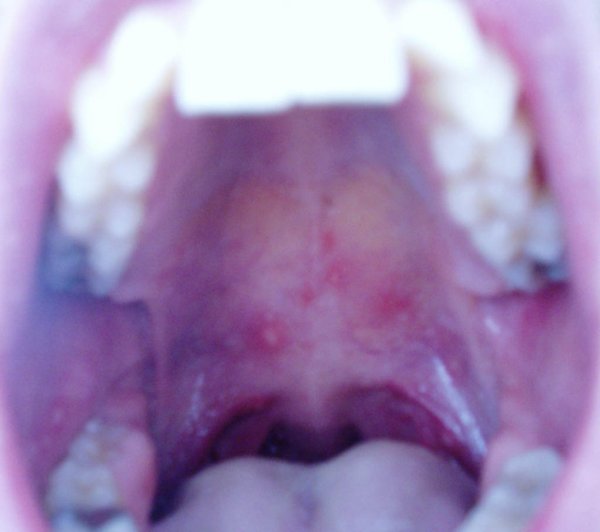

I had a fever, cough, sore throat, head ache, 23 mouth/throat ulcers

23 mouth/throat ulcers > ur kidding right? fecking ell

no, not kidding.

omg!

erhhhhhhhhhhhhhhhh

sounds and looks PAINFUL!

fecking hell, suppose there isnt anything u can take? i mean u cant cover your whole mouth with bonjella, ulcers are barstids take forever to heal

fine now. Corsodyl mouthwash and Difflam spray

I think this thread should have a warning with that pic!!!! hehe hope your feeling ok matey!! Should have had a really hot curry to kill em off